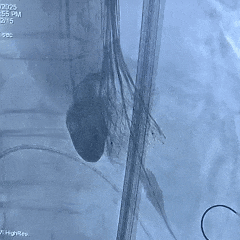

手术过程

左侧冠脉造影

右侧冠脉造影并行PCI

根部造影

可见瓣叶钙化,伴反流

TF21瓣膜0位初始释放

全展开后多角度根部造影:瓣膜深度形态合适,冠脉灌注良好,少量瓣周漏,选择解锁脱钩

脱钩后造影评估:瓣膜深度可,展开良好,少量瓣周漏

外周造影检查,血管无损伤